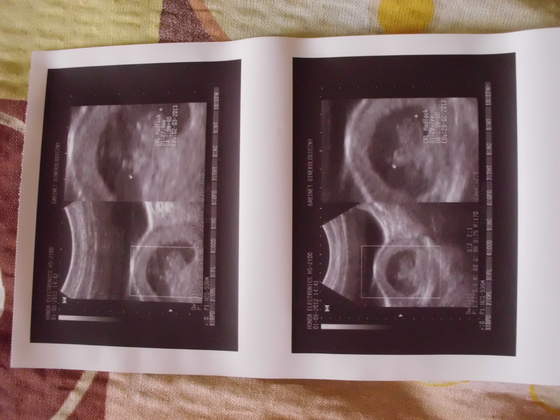

IMG_0453.jpg IMG_0454.jpgIMG_0455.jpgIMG_0456.jpg przedstawiam wszystkim cioteczką z bb moje małe szczęście:)